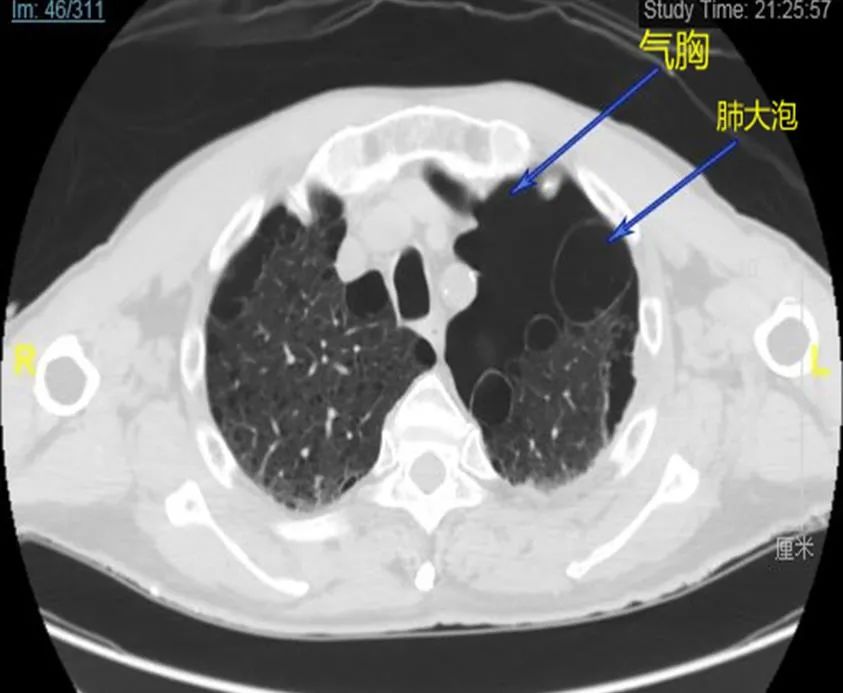

经过胸部CT及肋骨三维重建等检查,显示这是一个重度胸部创伤伴有自身肺部严重疾病的病例。车祸伤致左侧6根肋骨骨折、右侧3根肋骨骨折、肋骨断茬刺破肺产生胸腔积血积气(血气胸)。同时老人自身还有老年性肺气肿、左侧多发性肺大泡,这些肺大泡如同“定时炸弹”随时会破裂造成自发性气胸或血气胸(见图1 、2)。

图2 CT所见血气胸、多发性肺大泡